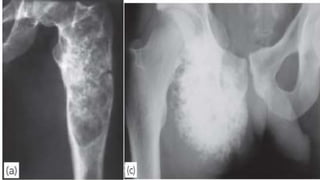

CHONDROSARCOMA

Chondrosarcoma occurs either as a primary

tumour or as a secondary change in a pre-

existing benign chondroma or

osteochondroma.

Chondrosarcomas have their highest incidence

in the fourth and fifth decades, and men are

affected more.

Patients may complain of a dull ache or a

gradually enlarging lump. or as a pathological

fracture.

X-ray examination shows a radiolucent area

EWING’S SARCOMA

Ewing’s sarcoma is believed to arise from endothelial cells

in the bone marrow.

It occurs most commonly between the ages of 10 and 20

years.

Occure usually in a tubular bone and especially in the

tibia, fibula or clavicle.

The patient presents with pain – often throbbing in

character – and swelling. generalized illness and pyrexia.

X-ray usually shows an area of bone destruction which is

predominantly in the mid diaphysis. New bone formation

may extend along the shaft and sometimes it appears as

fusiform layers of bone around the lesion – the so-called

CHONDROSARCOMA Chondrosarcoma occurs eitheras a primary tumour or as a secondary change in a pre- existing benign chondroma or osteochondroma. Chondrosarcomas have their highest incidence in the fourth and fifth decades, and men are affected more. Patients may complain of a dull ache or a gradually enlarging lump. or as a pathological fracture. X-ray examination shows a radiolucent area

EWING’S SARCOMA Ewing’s sarcomais believed to arise from endothelial cells in the bone marrow. It occurs most commonly between the ages of 10 and 20 years. Occure usually in a tubular bone and especially in the tibia, fibula or clavicle. The patient presents with pain – often throbbing in character – and swelling. generalized illness and pyrexia. X-ray usually shows an area of bone destruction which is predominantly in the mid diaphysis. New bone formation may extend along the shaft and sometimes it appears as fusiform layers of bone around the lesion – the so-called